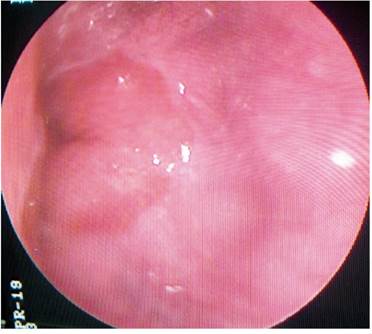

Paciente AMDA: mujer de 73 años con diagnóstico clínico de RGE, con antecedente de EPOC por exposición al humo de leña, uso permanente de inhaladores y oxígeno suplementario en casa. En el momento del examen físico se presenta con obesidad, cianosis de piel y mucosas y abotagamiento (Figura 2). En la EGD, se encontraron várices en los 6 primeros centímetros del esófago (Figura 3) con ausencia distal de estas (Figura 4), sin estigmas de sangrado o de riesgo y gastritis crónica superficial.

Otra causa de las várices proximales no descrita es la obesidad y su componente frecuente de SAHO, condiciones que son desencadenantes de HTP no obstructiva y estuvieron presentes en el 38 % y el 29 % de nuestros casos, respectivamente. Así pues, solo el 29 % de los casos contaban con un diagnóstico clínico de HTP: la mitad de ellos eran dependientes de oxígeno y otros dos sugerían la enfermedad, dado su aspecto clínico (cianosis, poliglobulia y abotagamiento) (Figuras2y6). Además, probablemente, también requerían de oxígeno suplementario.